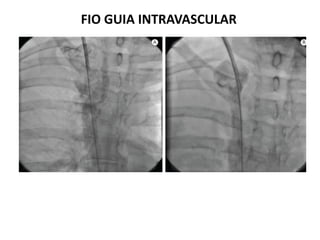

FIO GUIA INTRAVASCULAR

Contraindicação absoluta

* São maleáveis e sensíveis ao campo magnético.